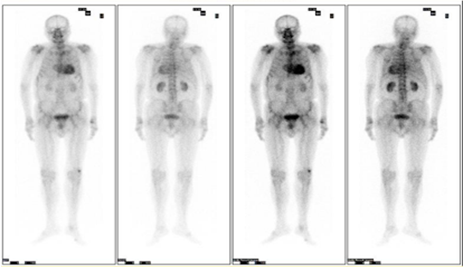

此次确诊的省内首例转甲状腺素蛋白心脏淀粉样变(ATTR-CA)患者为80几岁的王某(化名),因反复慢性心衰伴心律失常多年到我院就诊。入院后该患者的心脏彩超提示心肌肥厚,进行心脏核磁共振扫描结果提示心肌淀粉样变,接诊的干部特诊一科陈建康主任医师联合多学科为患者展开相应排查,使用了包括血清、基因检测、核素、核磁等一系列精准的诊断手段,抽丝剥茧、层层深入,最后诊断患者为野生型ATTR心脏淀粉样变性(ATTRwt),为后续的治疗提供了准确的依据。

▲病例心肌核素99mTc-PYP显像结果

临床上常根据有无TTR基因突变可以将ATTR-CA分为遗传型/突变型(ATTRm)和野生型(ATTRwt)。据心血管内三科卢荔红主任医师介绍,野生型心脏淀粉样变,又称之为老年性系统性淀粉样变,是一种罕见的导致心力衰竭的疾病,极易误诊为肥厚型心肌病、冠心病等,大部分ATTRwt患者的诊断年龄在70岁以上。